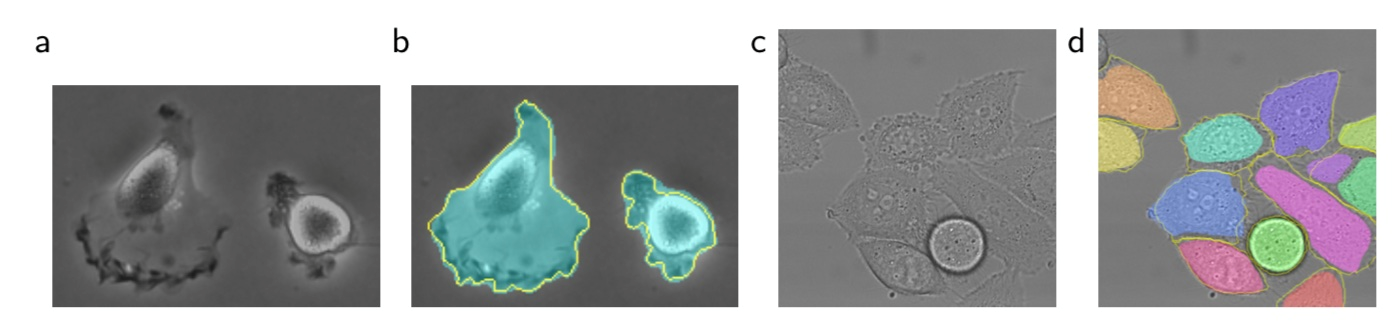

下面是U-Net在两种不同的分割任务中的应用效果

1、U-Net应用于光学显微图像中的细胞分割任务

ISBI细胞跟踪挑战的结果。(a)“PhC-U373”数据集的输入图像的一部分 (b)分割结果(青色掩模)和人工标注的GT(黄色边框) (c)“DIC-HeLa”数据集的输入图像 (d)分割结果(随机彩色掩模)和人工GT(黄色边框)

评估结果:包含35个部分注释的训练图像。实现了92%的平均IOU

其中“DIC-HeLa”另外一个数据集,这里不做介绍了。